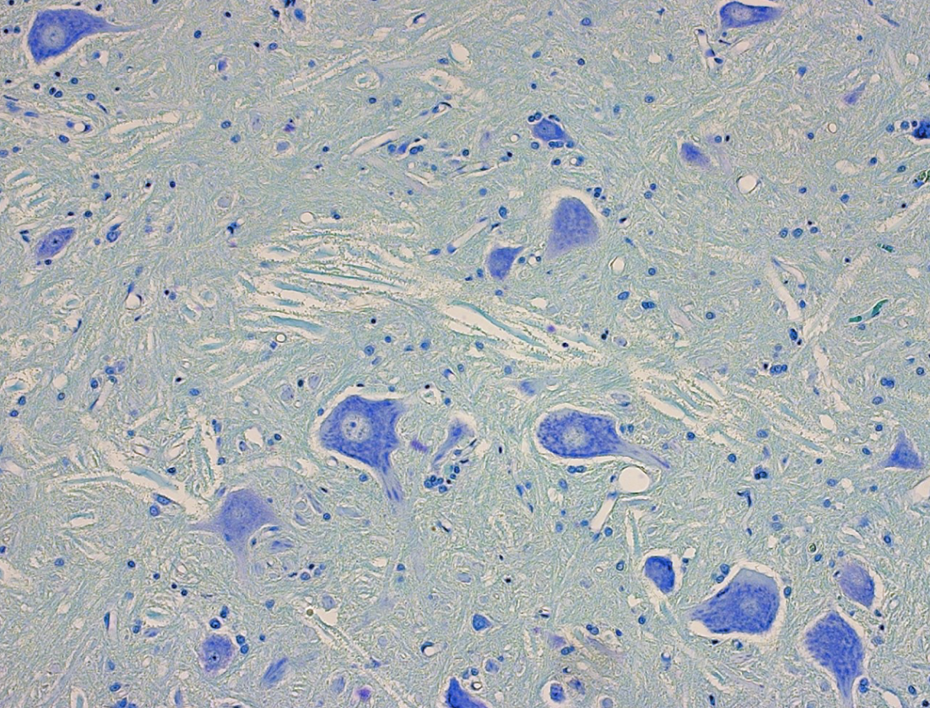

Blue –> nucleus

Black –> Dendrite

Yellow –> axon hillock

Red –> axon hillock